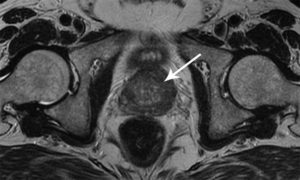

При раке простаты на МРТ-снимке визуализируются плотные скопления, которые отсутствуют при здоровом органе.

В ходе сканирования появляется возможность выявления формы онкологии. Например, слабый резонанс «говорит» о развитии опухоли, образованной клетками с муцином.

Для определения характера опухоли (злокачественной или доброкачественной) проводится биопсия.

МРТ снимок простаты (рак)